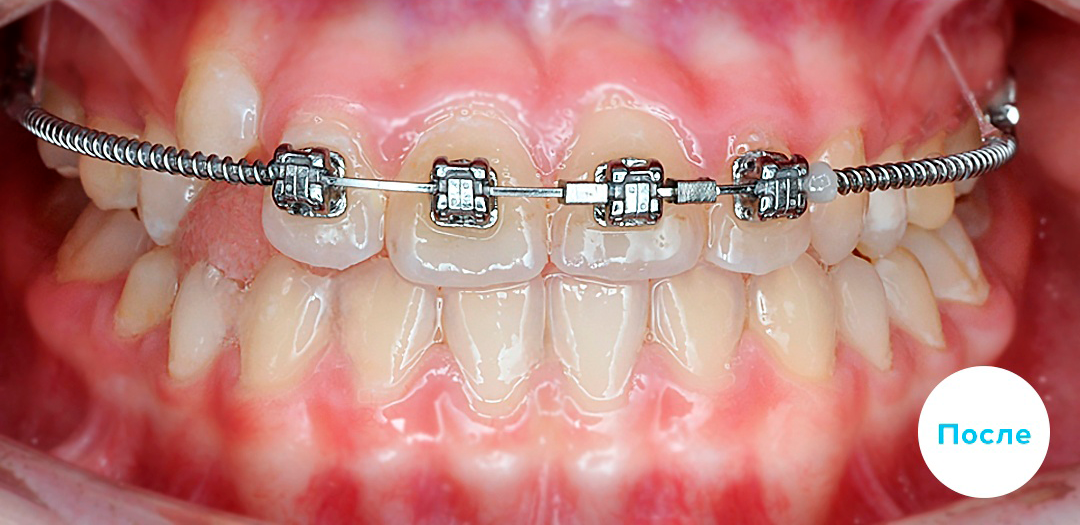

После

После

После